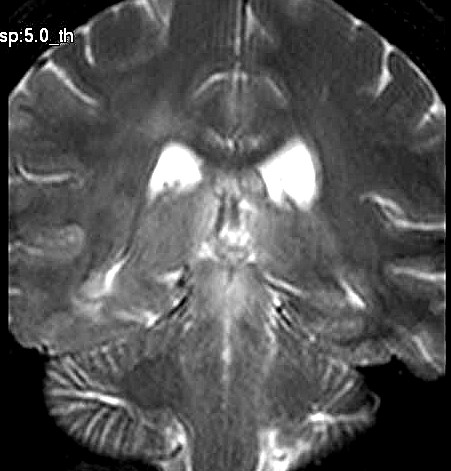

| Fem. 17a. |

| Nódulo sólido homogêneo preenchendo o III ventrículo, com limites precisos, com hipossinal em T1 e hipersinal em T2 e FLAIR, que se impregna por contraste paramagnético. Lesão menor implantada no assoalho do IV ventrículo provavelmente representa disseminação por via liquórica. |

| CORTES AXIAIS, T1 COM CONTRASTE | ||

| AXIAIS, FLAIR | T2 | |